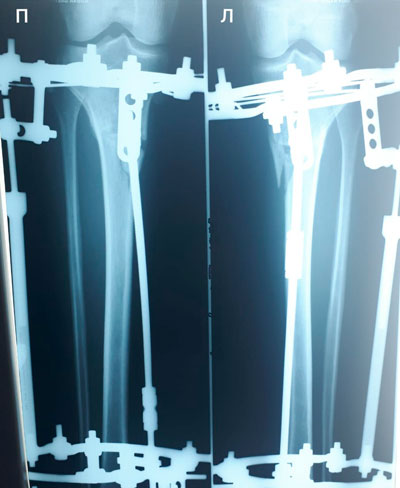

Рентген перед снятием аппаратов.

Дата операции - 20.03.2019г.

Дата снятия аппаратов - 04.07.2019г.

Срок сращения - 104 дня.